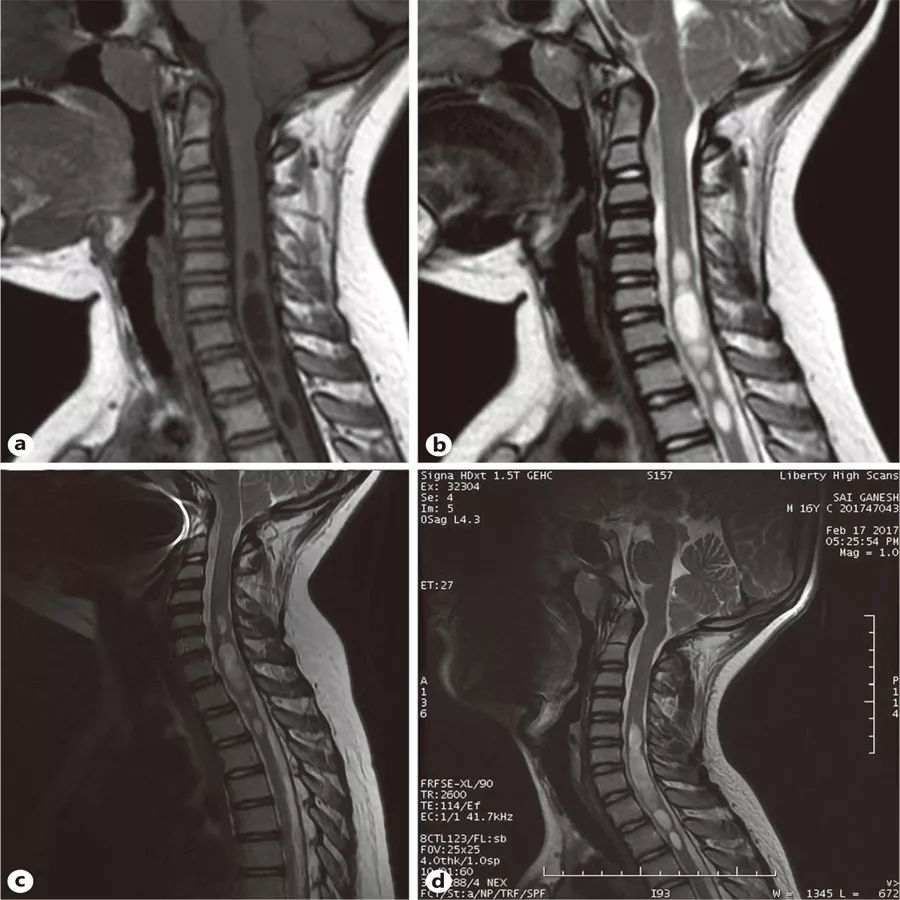

图1

患儿,男,8岁。在2010年首次做T1加权(A)和T2加权(B)MRI。在2017年再次做T1加权(C)和T2加权(D)MRI。到2017年,后脑疝从14毫米缩小到3毫米,脊髓空洞缩小,仅从C5延伸到T2。